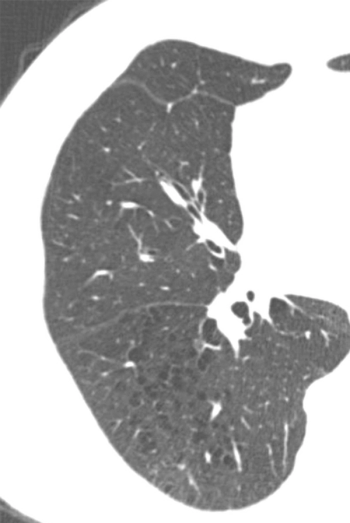

Based on imaging and other factors, researchers determine that lung health recovery is not linked to severity of COVID-19 illness.

Visual emphysema CT patterns at baseline can help providers determine how the condition will advance in both current and former smokers.